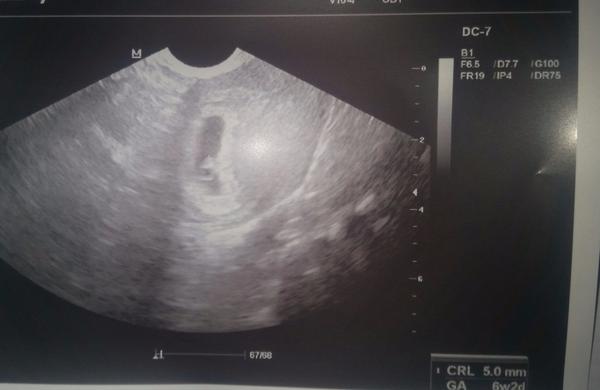

Holky dneska jsem byla na 1.kontrole. dle utz jsem 6+2. Mimisek je tam kde ma být a má 5 mm a už bilo srdíčko 😍 jako v té čekárně jsem myslela, že mi vyskočí srdce z hrudníku. Byla jsem hrozně nervozni. Ale ťuk ťuk ťuk je to vše v pořádku a 2.5. jdu na odběry krve 😉